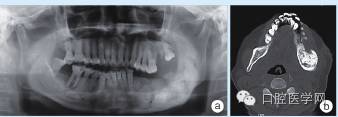

入院检查:混合牙列,11-12牙区见唇腭侧牙槽骨膨隆,腭侧较明显,表面黏膜颜色正常,触诊质地硬,无压痛感。辅助检查:全颌曲面断层片及CT显示11牙胚存在,其冠方牙槽骨内高密度团块影,周围可见低密度带,与周围骨组织分界清(图2a、b)。

图2 a:全颌曲面断层片;b:CT影像